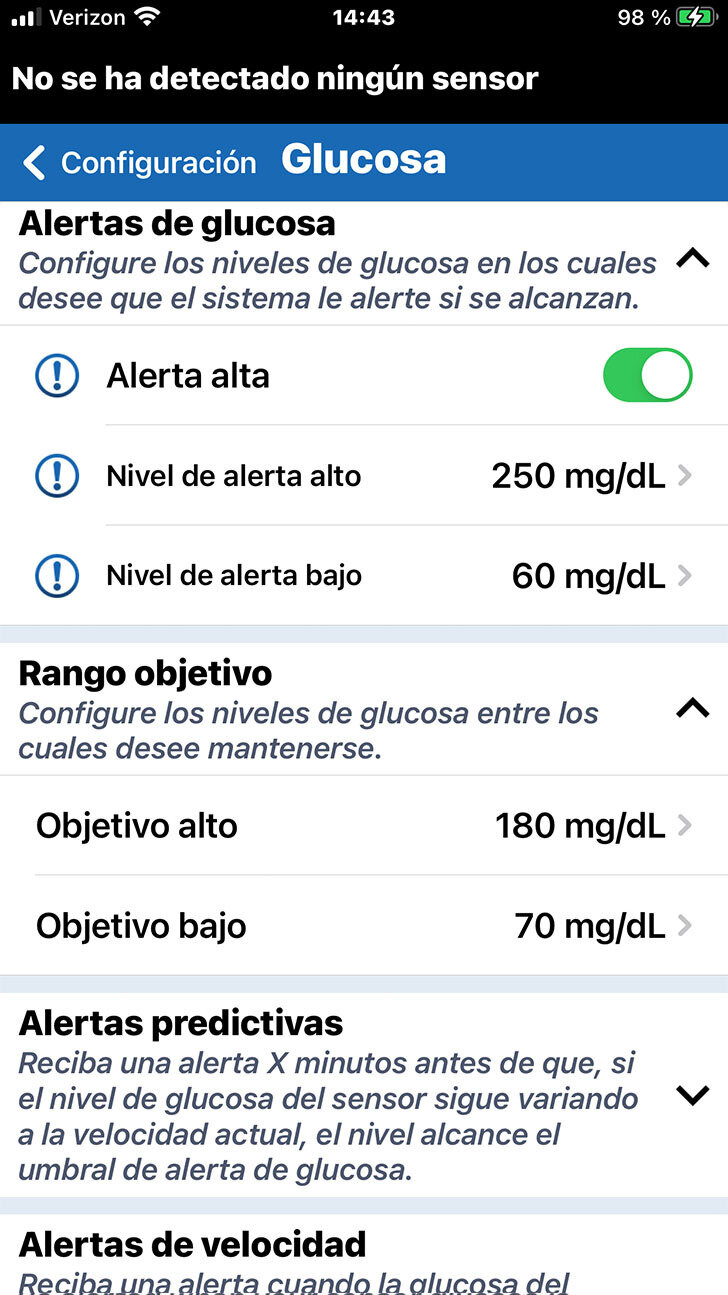

Al entrar en la configuración de la glucosa, verá la sección de Alertas

de glucosa en la parte superior.

Las alertas de glucosa le permitirán saber si su nivel de glucosa ha superado un umbral de glucosa alto o bajo crítico, según lo determine el profesional de la salud.

Tenga en cuenta que la configuración predeterminada es 250 mg/dL en el caso de la alerta de glucosa alta y de 65 mg/dL en el de la glucosa baja.

Al entrar en la configuración de la glucosa, verá la sección de Alertas

de glucosa en la parte superior.

Las alertas de glucosa le permitirán saber si su nivel de glucosa ha superado un umbral de glucosa alto o bajo crítico, según lo determine el profesional de la salud.

Cuando desee personalizar la configuración de una alerta de glucosa, solo deberá tocar el ajuste que desee modificar.

Desplácese al valor deseado. A continuación, toque OK.

Siempre analice con su profesional

de la salud la configuración de las alertas adecuada para usted.

Cuando desee personalizar la configuración de una alerta de glucosa, solo deberá tocar el ajuste que desee modificar.

Debajo de Alertas de glucosa puede configurar su Intervalo objetivo de glucosa.

El intervalo objetivo de glucosa es la zona en la que tanto usted como el profesional de la salud deciden que deben estar sus niveles de glucosa la mayor parte del tiempo.

PERSONALICE LOS OBJETIVOS DE GLUCOSA

Nuevamente, solo tiene que tocar en el ajuste que le gustaría modificar, desplazarse hasta al valor deseado y, finalmente, tocar OK.

Debajo de Alertas de glucosa puede configurar su Intervalo objetivo de glucosa.

El intervalo objetivo de glucosa es la zona en la que tanto usted como el profesional de la salud deciden que deben estar sus niveles de glucosa la mayor parte del tiempo.

Tenga en cuenta que los niveles objetivo

de glucosa solo se pueden programar dentro de los niveles de alertas

de glucosa que ha definido.

Nuevamente, solo tiene que tocar en el ajuste que le gustaría modificar, desplazarse hasta al valor deseado y, finalmente, tocar OK.

Debajo de Alertas de glucosa puede configurar su Intervalo objetivo de glucosa.

El intervalo objetivo de glucosa es la zona en la que tanto usted como el profesional de la salud deciden que deben estar sus niveles de glucosa la mayor parte del tiempo.

En esta pantalla, también puede definir alertas predictivas y de velocidad de cambio.

Las alertas predictivas pueden

ser especialmente útiles para

los usuarios de la MCG.

No obstante, si es su primera vez con

la MCG, puede que lo mejor sea esperar para configurar estas alertas opcionales hasta que hable de estos ajustes con

su profesional de la salud.

Consulte la Guía del usuario para obtener más información.